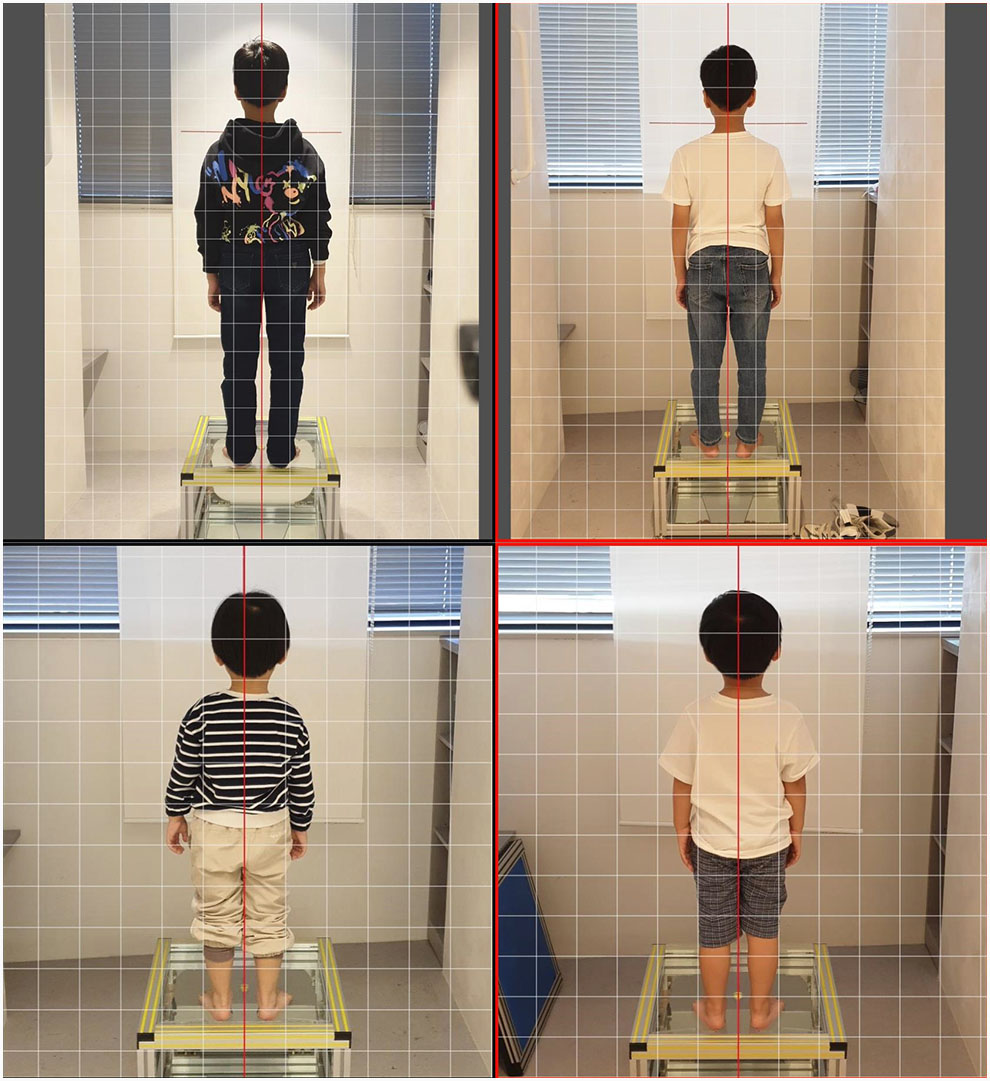

턱 균형이 자리 잡힌다면 어떤 변화가 있는지 기록한 자료들이 있습니다.

뿐만 아니라 얼굴부터 시작해 몸 전체적으로 좌우 대칭성이 개선되었습니다.

힘을 뺀 상태에서 가만히 서 있을 때 한쪽으로 기우는듯한 증상이 있다면 해당 치료법이 도움 될 것입니다.